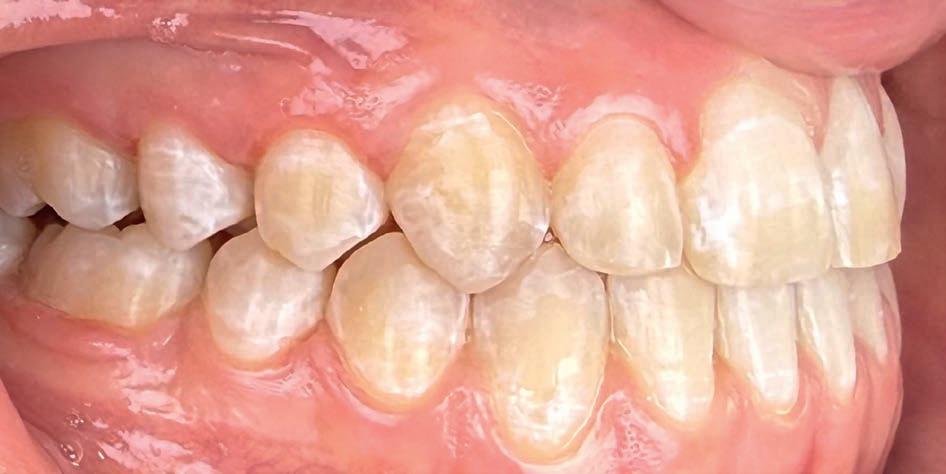

Casus: Jorn

Niet-chirurgische correctie van een Klasse III-relatie

Patiënt: Jorn (18 jaar)

Behandelduur: 15 maanden

Behandeling: Damon Ultima brackets en elastieken

Jorn en zijn vader kwamen via Google bij Clover

Orthodontie terecht, nadat hij elders een chirurgisch behandelvoorstel had gekregen. Als actieve voetballer paste een operatie niet in zijn leven. Hij presenteerde zich met een skeletale Klasse III-relatie, anterieure kruisbeet, negatieve sagittale overbeet en een concaaf profiel.

Behandelstrategie

Er werd gekozen voor een behandeling met Damon Ultima brackets en een strak gepland elastiekprotocol. Vanaf het begin droeg Jorn Klasse III-elastieken om de sagittale discrepantie te corrigeren. Dankzij de precisie en lage frictie van Damon Ultima konden we transversaal én sagittaal corrigeren zonder chirurgische ingreep.

Het eindresultaat bestond uit een stabiele Klasse I-occlusie met een duidelijk verbeterd profiel. Er zijn geen extracties of chirurgische ingrepen uitgevoerd. Voor de retentie werd gekozen voor vaste spalken in combinatie met nachtbeugels, om het bereikte resultaat langdurig te behouden.